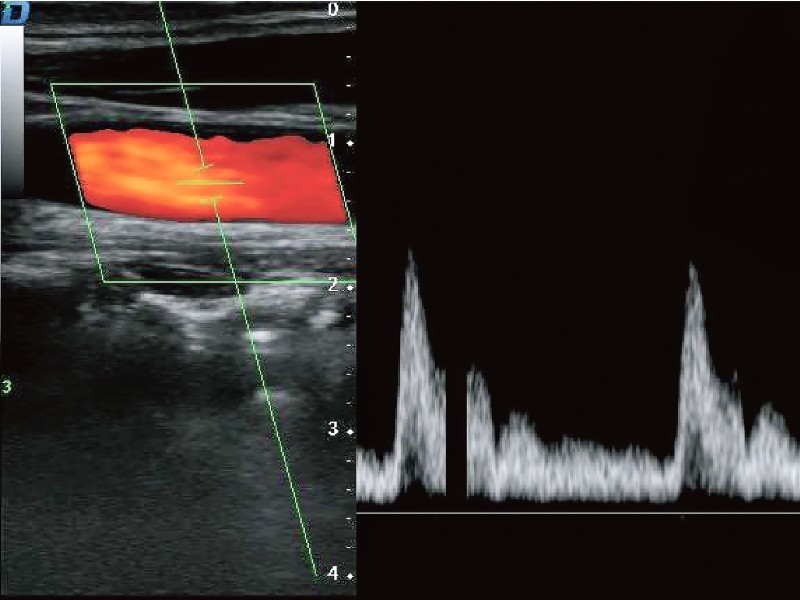

指向性パワードップラーイメージング (DPDI)